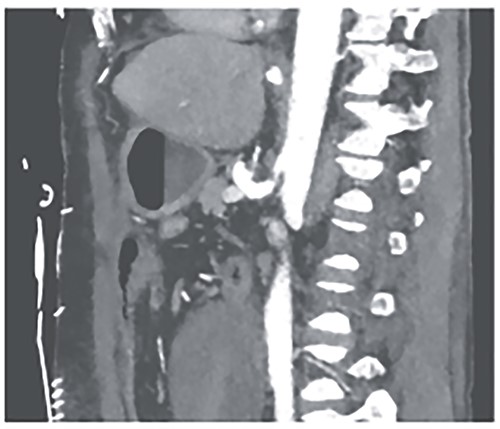

However, on the 16th day following the initial surgery, there was another active bleeding from the pancreaticoduodenal artery, distal to the previously placed coil. This bleeding was also managed interventionally (Figs 4 and 5).

Angiography showing another aneurysm with active bleeding, proximally to the previously coiled site.